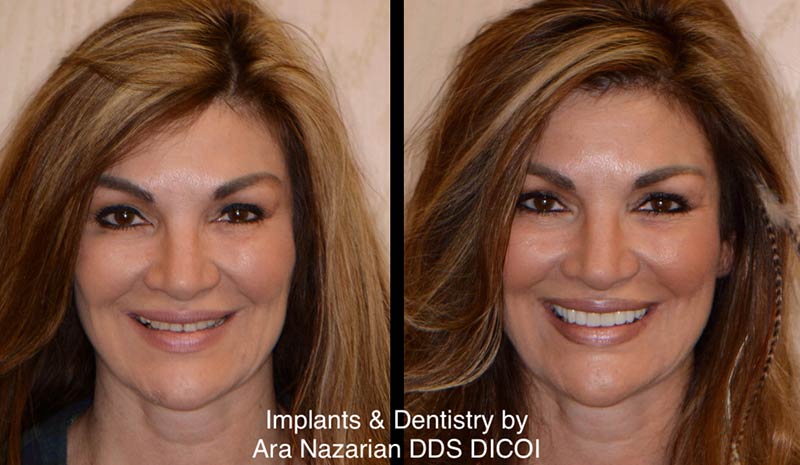

If you’ve ever felt self-conscious about your smile, request an appointment with our cosmetic dentist. Dr. Nazarian understands the embarrassment some patients can have about their oral health and is ready to help.

Accommodating the Cosmetic Patient

The goal of cosmetic dentistry is to improve the appearance of teeth that show when you smile and talk. The goal of full mouth reconstruction is more expansive because it focuses on restoring the function of teeth, gums, and jaws.

As a dental implant dentist, Dr. Nazarian strives to be the best dental health provider he can be. His goal is to provide what the patient wants as much as possible. It is the strength of that relationship and the quality of communication and education that influences the final outcome of nearly any complex treatment.

Cosmetic and Reconstructive Case History Example

Since this patient was born and raised in a foreign country, she didn’t have access to orthodontic treatment. A history of treating common childhood illnesses also caused the dark bands of staining on almost all of her teeth (severe tetracycline stains).

Cosmetic and Reconstructive Drama

The combination of short-term orthodontic straightening and bite opening moved the jaw into the position that Mother Nature failed to produce. Lastly, Dr. Nazarian’s choices of veneers and porcelain crowns on different tooth structures assure that occlusion-caused breakage will not occur.

Patients who have had significant issues with a bad or a disturbed bite will tend to focus more on the functional aspects of treatment. As with most reconstructive dentists who thrive on achieving the most dramatic results possible with any given choice of treatments and products, Dr. Nazarian maintains a watchful eye on the dynamics of change desired by patients.

Patients who prefer cosmetics over function are assured bite factors are factored into aesthetic treatments. Patients who are addressing major bite correction or alignment issues are provided with a choice of reconstructive components that are attractive and complement the functional changes.